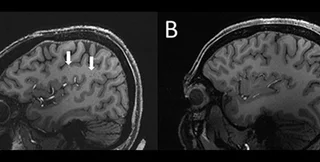

Стрелки показывают увеличенные периваскулярные пространства в головном мозге человека с хронической мигренью (слева) по сравнению с мозгом здорового человека (справа)

Результаты исследования показали, что периваскулярные пространства в мозге этих людей были значительно увеличены по сравнению с такими же пространствами в мозге здоровых добровольцев, которые были контрольной группой в исследовании.